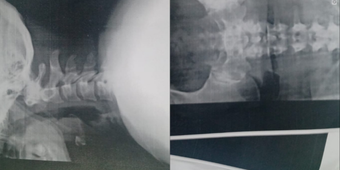

Olá, sou Pâmela filha da dona Eliane e criei essa vaquinha para arrecadar R$6.000 para poder pagar seus exames e medicamentos, descobrimos um grave problema na coluna cervical e lombar, ela precisa … [+214 chars]